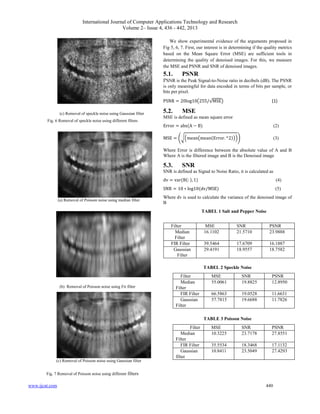

(a) Removal of Poisson noise using median filter

(b) Removal of Poisson noise using Fir filter

(c) Removal of Poisson noise using Gaussian filter

Fig. 7 Removal of Poisson noise using different filters

We show experimental evidence of the arguments proposed in

Fig 5, 6, 7. First, our interest is in determining if the quality metrics

based on the Mean Square Error (MSE) are sufficient tools in

determining the quality of denoised images. For this, we measure

the MSE and PSNR and SNR of denoised images.

TABEL 1 Salt and Pepper Noise

TABEL 2 Speckle Noise

Filter MSE SNR PSNR

Median

Filter

55.0061 19.8825 12.8950

FIR Filter 66.5863 19.0528 11.6631

Gaussian

57.7815 19.6688 11.7826

TABLE 3 Poisson Noise

10.3225 23.7178 27.8551

FIR Filter 35.5534 18.3468 17.1132

10.8411 23.5049 27.4293

16.1102 21.5710 23.9888

FIR Filter 39.5464 17.6709 16.1887

29.4191 18.9557 18.7582

To evaluate the filter effectively, three main statistical measures are

used. They are PSNR, MSE, and SNR. To compare these output

values and find out the better filtering result of denoised X-ray

images.

In table 1 the performance of various filter for salt and pepper

noise. Each filter in table 1 is tested and compared with other type

of filter by using of output value of PSNR, MSE, and SNR. In this

median filter technique is comparatively good for high density

noise. It is observed that the filter have PSNR and SNR is high

compared to other filters and also it have low MSE value.

The second categories of the filtering method for the speckle noise

has taken for the discussion and performed with three types of

filters are shown in table 2. Median filter gives best result compared

with other type of filters. In overview of all the filters in table2,

median filter gives much improved results and providing a high

degree of performance.

The third categories of this filtering method for the Poisson noise

are shown in table 3. Here also median filter gives a high

performance other than other type of filters.